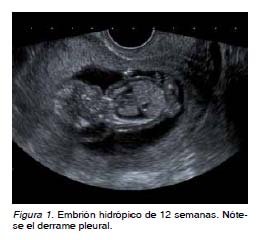

Se trata de una gestante de 38 años de edad, sin historial de consanguinidad, Rh positivo y con esterilidad primaria. Es remitida con un embarazo conseguido mediante técnicas de reproducción asistida a la Unidad de Ecografía en la semana 12, por translucencia nucal patológica. La paciente refiere dos abortos previos de 13 semanas y ambos de sexo masculino. En la ecografía de control en la semana 12 aparece una gestación única, intrauterina, activa, acorde a 12 semanas. La translucencia nucal es de 5 mm, de aspecto tabicado, en el contexto de un hidrops masivo (hidrotórax y ascitis), sin objetivarse otras alteraciones estructurales (Figura 1). Se solicita entonces estudio serológico, que fue negativo para toxoplasma, rubéola, citomegalovirus, herpes virus y parvovirus B19, y se aconseja cariotipo fetal mediante biopsia corial, donde se confirma que se trata de un embrión de sexo masculino (46XY). Mediante anamnesis exhaustiva, la paciente refiere y se objetivan lesiones hipopigmentadas en sus miembros inferiores acompañadas de ausencia de vello (Figura 2).